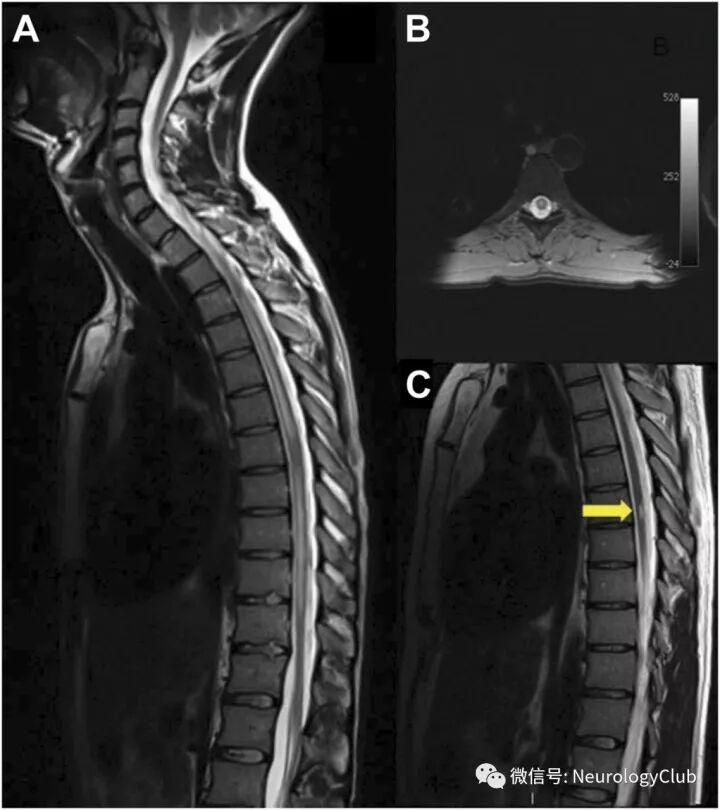

脊髓受累

(图27:NBD患者脊髓受累;A:T2WI可见全脊髓多发高信号病灶;B:增强后可见片状强化;C:治疗后病灶基本消失)

(图28:长节段脊髓受累的NBD患者;A:T2WI可见脊髓T3-L2异常信号;B:增强后病灶强化;C:10月后复查可见局部胶质增生不伴强化)

(图29:长节段脊髓受累的NBD患者T2WI横断面可见“百吉饼征”,或与静脉怒张有关,可能为其特征性影像,有助于与其他长节段脊髓病变,如视神经脊髓炎谱系疾病等鉴别